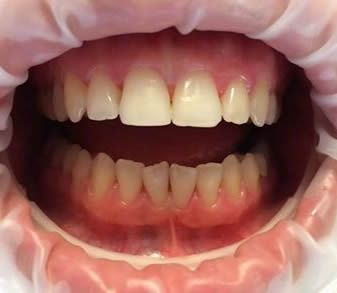

Ağız ve Diş sağlığınız için tüm hizmetleri burada bulabilirsiniz. Memnuniyetiniz de yanınıza kar kalacak.

Alanında uzman ve tecrübeli hekimlerimiz ile emin ellerdesiniz